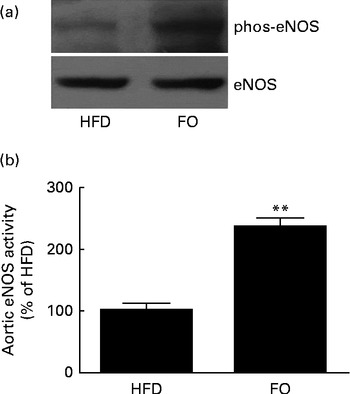

generation, NO release from single aortic endothelial cells was higher in the FO group (238·6 (sd 28·5) nm) than in the HFD group (112·7 (sd 15·8) nm) (P< 0·01). Cyclic GMP concentration in the aorta was higher in FO-fed mice (57·1 (sd 3·02) pm/mg protein) than in HFD-fed mice (7·10 (sd 1·02) pm/mg protein) (P< 0·01). Increased NO availability was associated with greater activation of endothelial NO synthase Ser-1177 phosphorylation levels (Fig. 6(a)) and endothelial NO synthase activity (Fig. 6(b)) in FO-fed mice compared with HFD-fed mice. Furthermore, aortic ONOO− levels were reduced in FO-fed mice (71·3 (sd 11·3) nm) compared with HFD-fed mice (130·9 (sd 10·5) nm) (P< 0·01).

generation, NO release from single aortic endothelial cells was higher in the FO group (238·6 (sd 28·5) nm) than in the HFD group (112·7 (sd 15·8) nm) (P< 0·01). Cyclic GMP concentration in the aorta was higher in FO-fed mice (57·1 (sd 3·02) pm/mg protein) than in HFD-fed mice (7·10 (sd 1·02) pm/mg protein) (P< 0·01). Increased NO availability was associated with greater activation of endothelial NO synthase Ser-1177 phosphorylation levels (Fig. 6(a)) and endothelial NO synthase activity (Fig. 6(b)) in FO-fed mice compared with HFD-fed mice. Furthermore, aortic ONOO− levels were reduced in FO-fed mice (71·3 (sd 11·3) nm) compared with HFD-fed mice (130·9 (sd 10·5) nm) (P< 0·01).

Fig. 6 Endothelial NO synthase (eNOS) expression and activity in the aortas. (a) Representative Western blots of Ser-1177 phosphorylation (phos) levels of eNOS. The blots are representative of six mice. HFD, high-fat diet; FO, high-fat diet enriched with 10 % fish oil. (b) eNOS activity in the aortas from the HFD group was defined as 100 %, and the same activity in the FO group was expressed as a percentage change of this control value. ** Mean value was significantly different from that of the HFD group (P< 0·01).